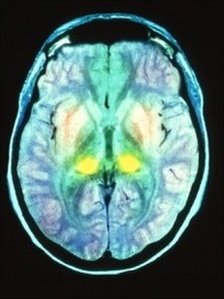

Variant Creutzfeldt-Jakob disease is a terrible legacy of the BSE outbreak. The fatal degenerative brain disorder is the human form of Bovine Spongiform Encephalopathy, commonly referred to as "mad-cow disease". It first emerged in 1995. The disease, which affects the brain, is believed to have passed from cattle to humans through consumption of meat products contaminated with BSE.

The issue gets little publicity these days, but news in The Lancet medical journal of a prototype blood test for the condition is a significant moment. Researchers at the Medical Research Council Prion Unit at University College London have managed to devise a test which can spot the infectious proteins - prions - responsible.

Prions, which cause vCJD and other fatal diseases, can inhabit a person's body for 50 years before presenting symptoms. So there has always been a suspicion that the true scale of the vCJD infection has remained hidden. A study of tonsil samples suggested that 1 in 4,000 Britons might have the disease, but no-one really knows whether that is an accurate estimate (opens pdf). One positive fact is that the number of deaths from vCJD has been falling steadily since a peak of 28 in 2000.

Variant CJD is a fatal condition for which there no proven treatment - although a number of experimental therapies have been tried. But there is scope for optimism here as well. Professor John Collinge, Director of the MRC Prion Unit was interviewed on Today on Radio 4 (listen again here). He said his team has been able to create human antibodies to the prion protein which blocked the disease in mice. Human clinical trials will begin in due course. Professor Collinge said: "There is an opportunity if we find people who are incubating the disease, in principle, to rescue them before they develop the disease itself."